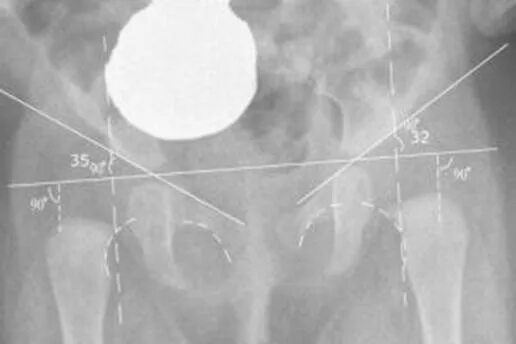

Дисплазия тазобедренного сустава мкб 10